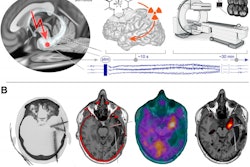

Researchers have developed a method to integrate functional MR (fMRI) and PET images to identify epilepsy patients who are at high risk of continued seizures before the patients undergo potentially unsuccessful surgery, according to a study published online December 5 in Frontiers in Neuroscience.

Statistician Marina Vannucci, lead author Dr. Sharon Chiang, and colleagues from Rice University and Baylor College of Medicine created a model from PET and resting-state fMRI scan data using 51 patients from the University of California, Los Angeles (UCLA) Seizure Disorder Center between 2007 and 2012.

Chiang and colleagues used statistical techniques to analyze brain activity data from patients with epilepsy and from groups of healthy controls. They found that the recurrence of seizures after surgery may be due to surgical disruption of fibers connected to previously normal brain tissue or incomplete resection of an epileptogenic network.